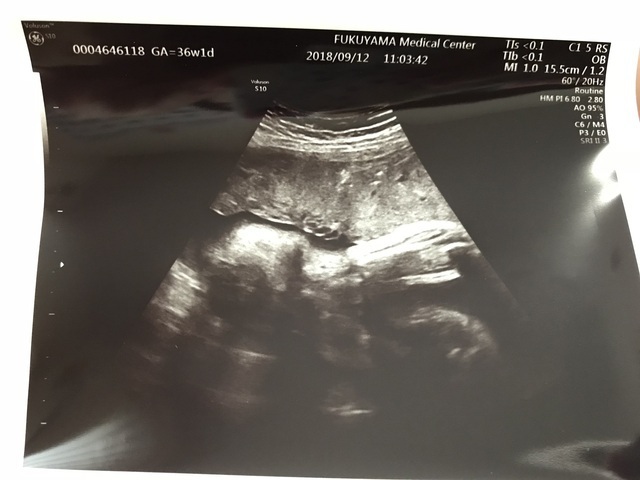

36週1日(36w1d・女の子)|aya.i さん(27歳)

エコー写真撮影時のエピソード:

29週の頃、羊水過少で緊急入院になりました。約半月入院したけど、原因は分からず、、、里帰り出産を希望しており、34週の時、実家に帰りました。初めての里帰り先での病院受診で、帝王切開になる事が決まり、その次の週に今回のエコー写真が撮られました。まだ出てきたくないのか、両手で顔を隠していました。予定日より3週間早く、37週の時に無事生まれてきてくれて、エコー写真と同じように顔に手を置いていました。